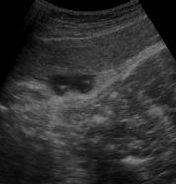

影像圖破膜後胎心率突然變慢,臍帶脫垂的可能性很大,應立即做肛查和(或)陰道檢查如發現宮口內有搏動的粗如手指的索狀物即為臍帶先露。如臍帶脫出於宮頸口之外,臍帶脫垂即可確診。檢查者的手觸摸臍帶搏動,可監測胎兒在宮內的情況。不能用力觸摸以免加重臍帶受壓。